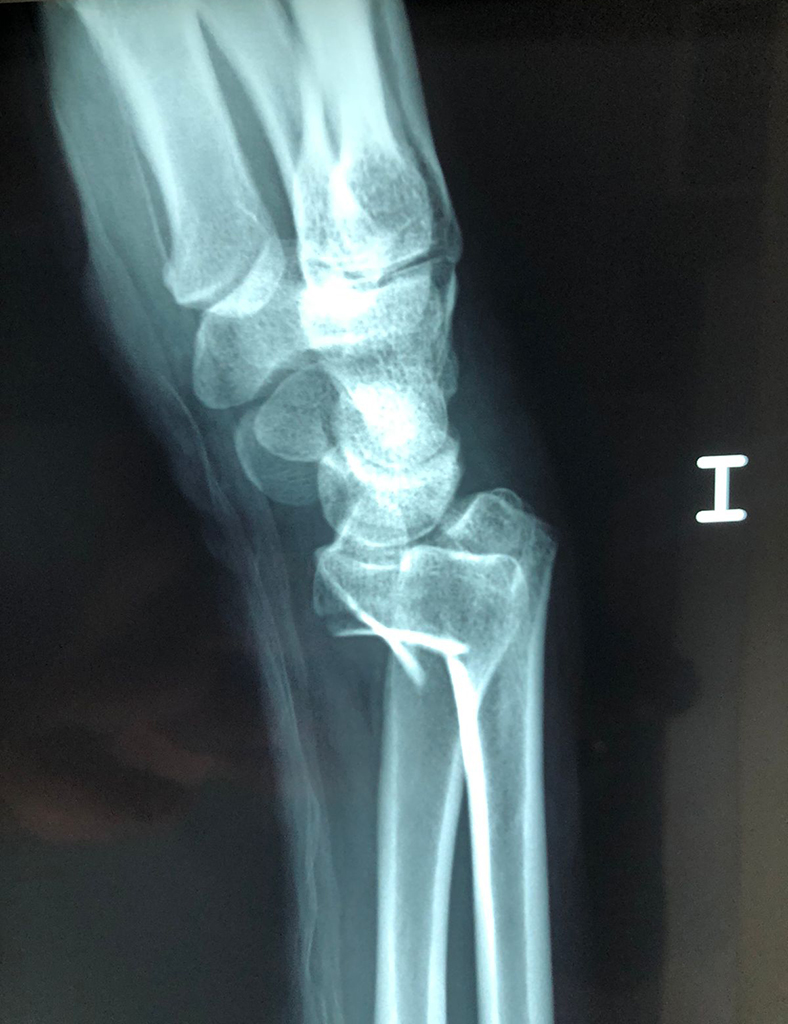

Cirugía de Muñeca y Mano

Los procedimientos más comunes en cirugía de la mano son aquellos destinados a reparar traumatismos, incluyendo lesiones de tendones, nervios, vasos sanguíneos, y articulaciones; huesos fracturados; y quemaduras, cortes, y otros daños de la piel.